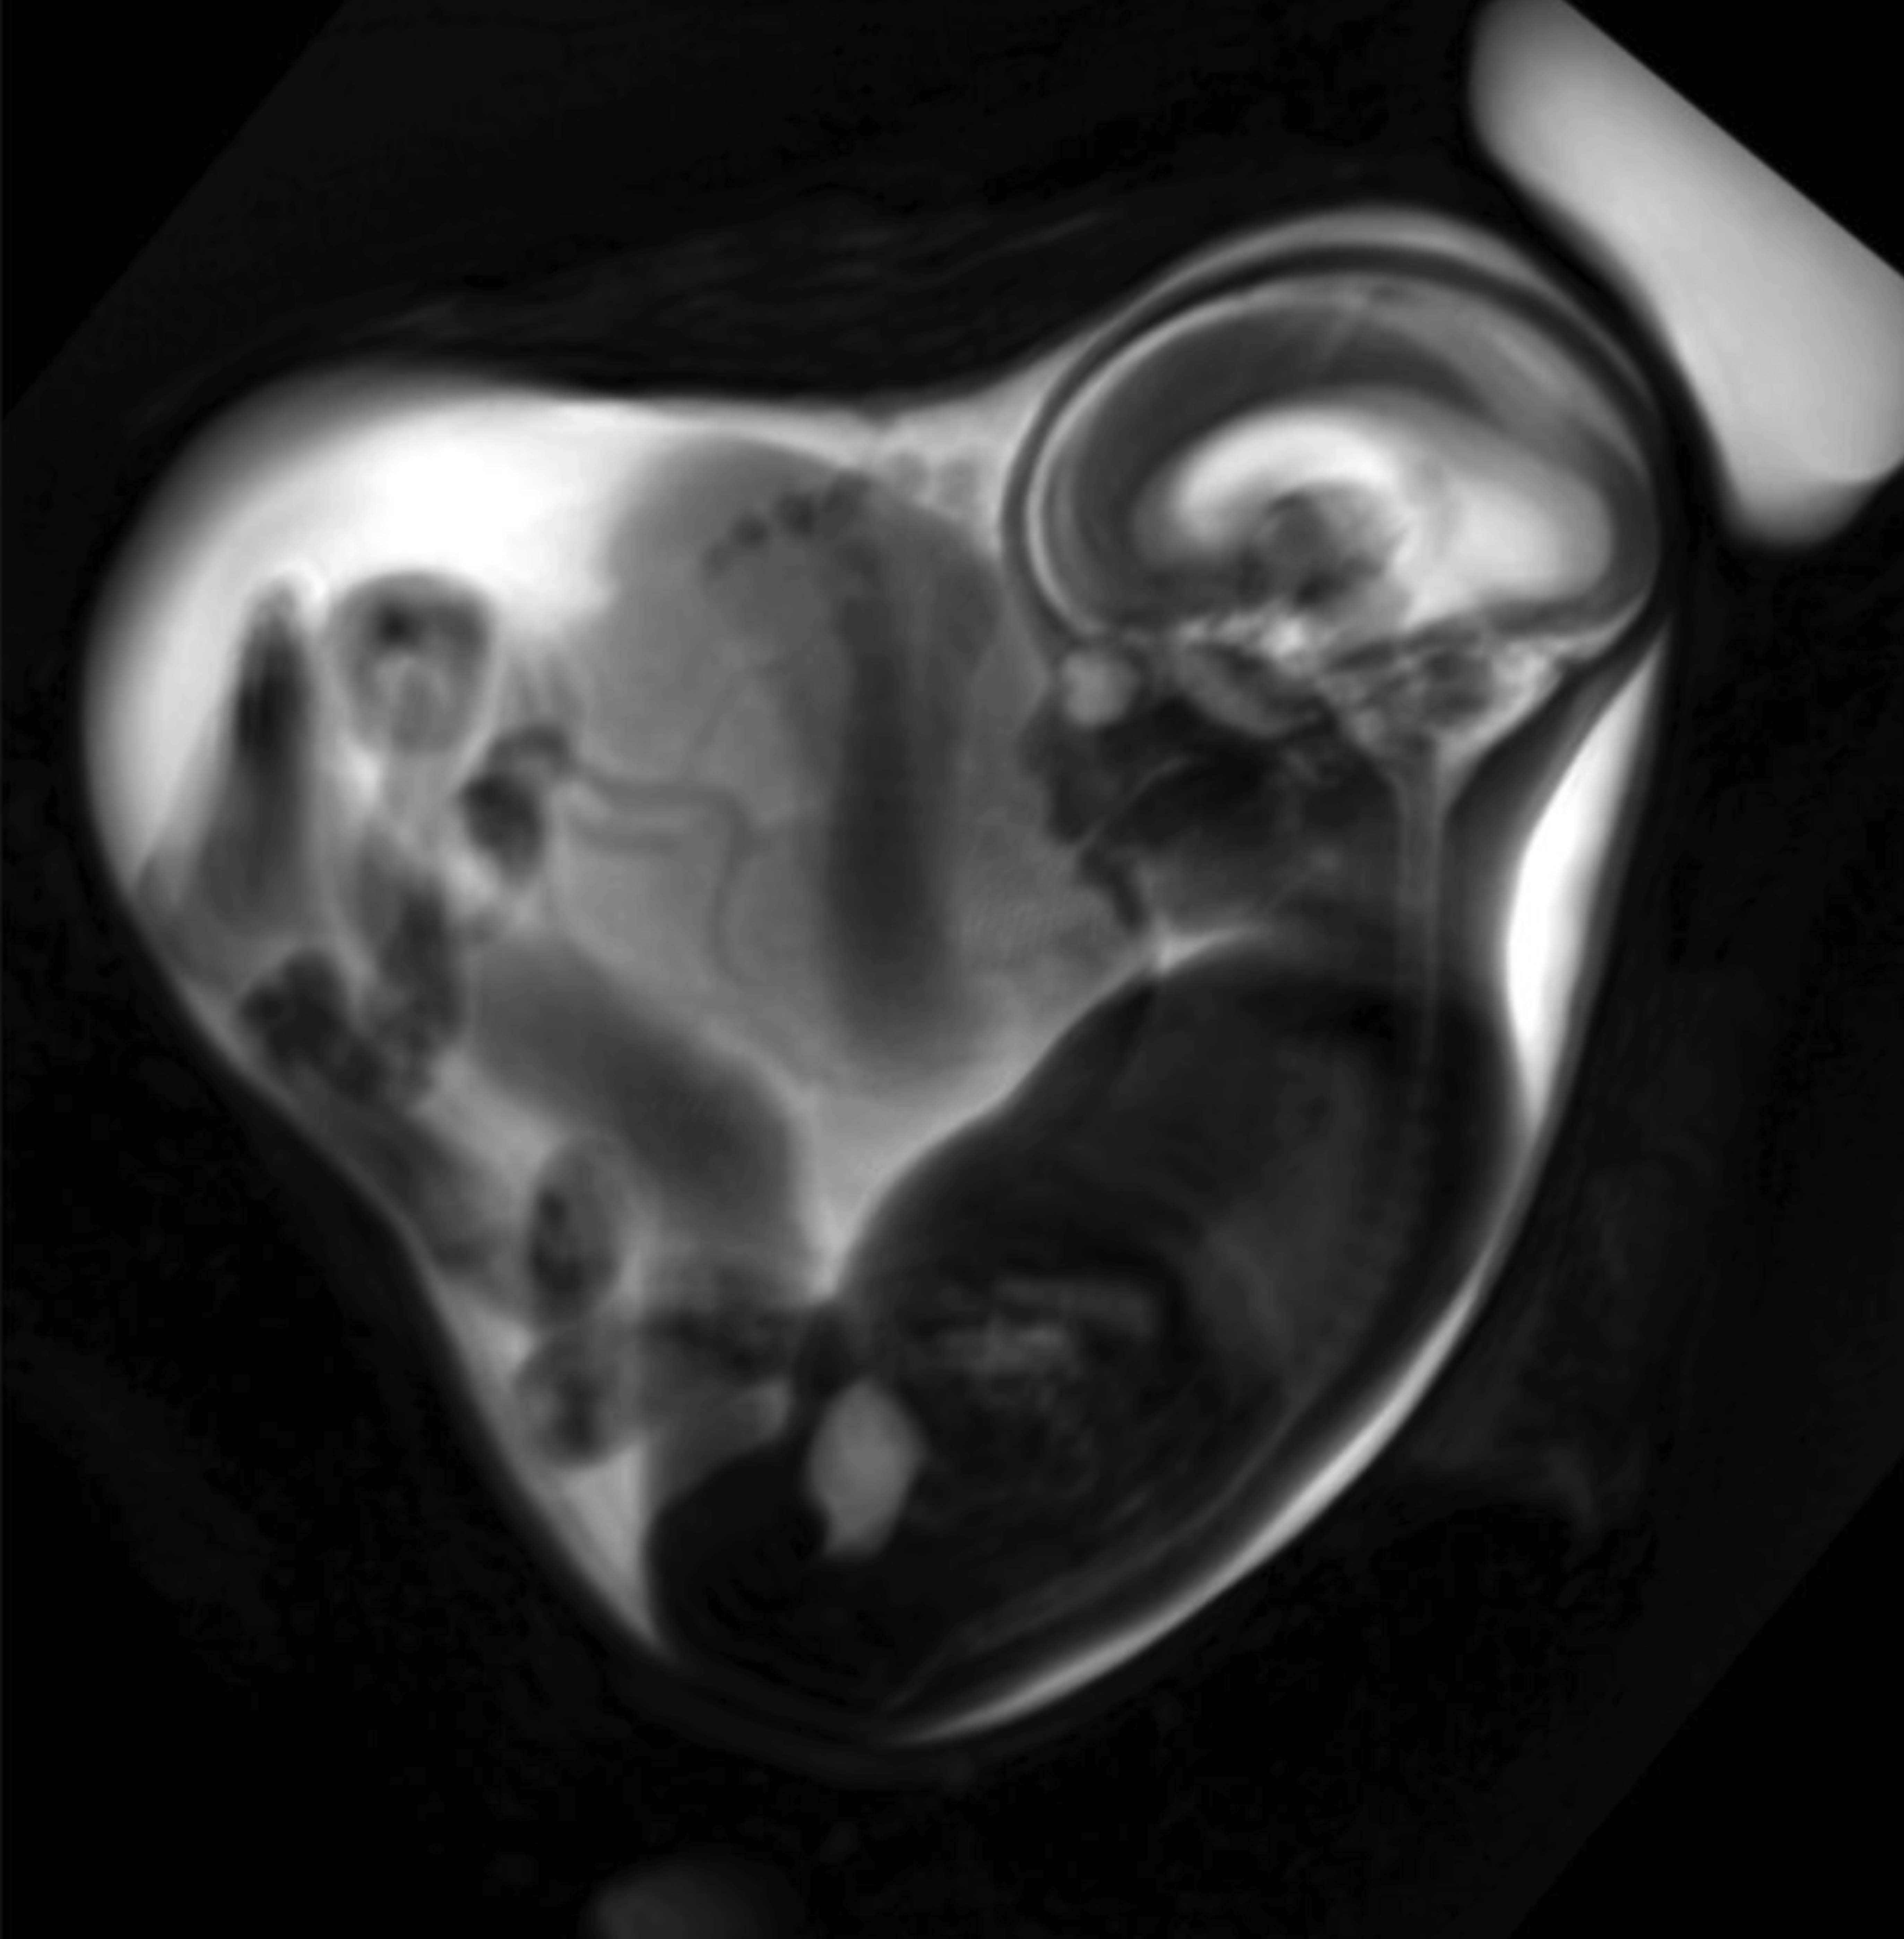

Led by Professor Sophia Stoecklein, Department of Radiology (LMU University Hospital Munich) and PD Dr. Anne Hilgendorff, Centre for Comprehensive Developmental Care (LMU University Hospital Munich) and Helmholtz Munich, researchers examined a total of 34 pregnant women and fetuses using fetal MRI. The women were infected with the SARS-CoV-2 Alpha variant at different stages during pregnancy, as confirmed by PCR testing. Fetal MRI is a highly specialized prenatal imaging method that enables the detailed evaluation of fetal organs and tissue, demonstrating a reduction in lung volume in fetuses from SARS-CoV-2 pregnancies – as compared with fetuses from an uninfected reference cohort.

“The fetuses of pregnant women who tested positive for SARS-CoV-2 had an overall lower lung volume compared to the reference cohort,” says Professor Stoecklein. The effect was particularly pronounced in third-trimester fetuses, where an average of 69 percent of the expected average for normal lung volume was noted.